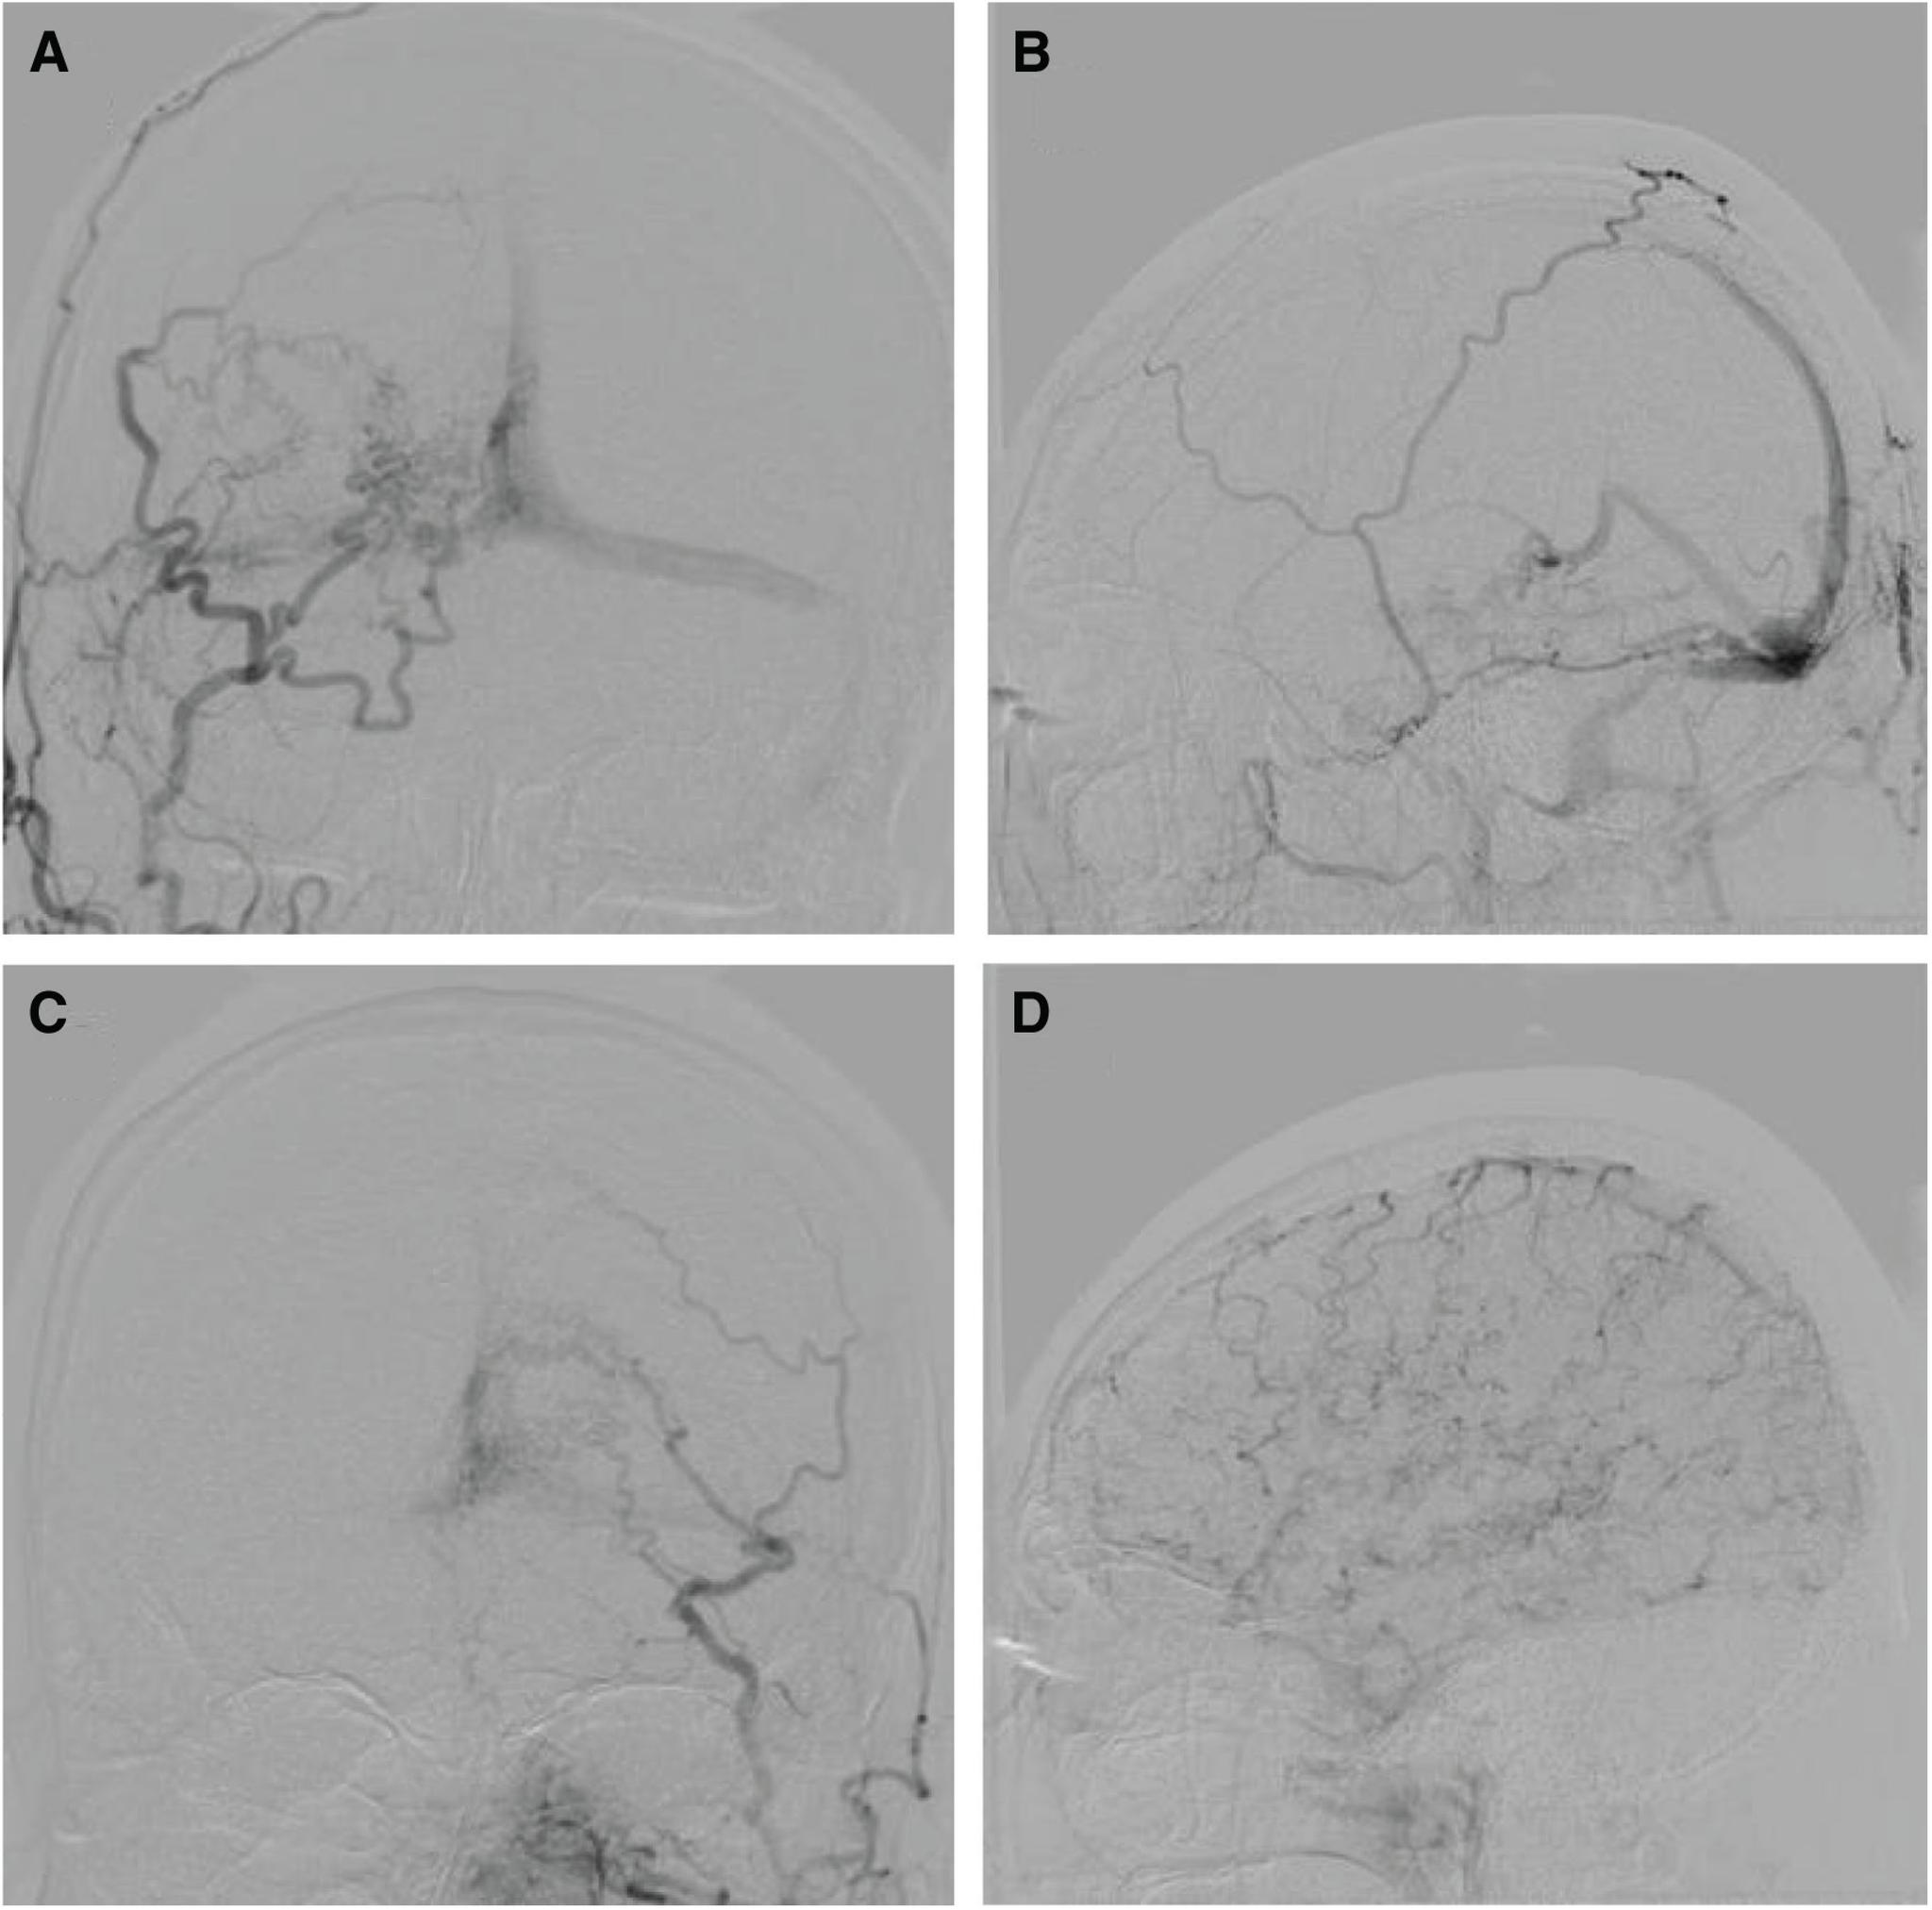

The patient was a 65-year-old man. Cerebral angiography demonstrated an aggressive dAVF involving the TSS, superior sagittal sinus (SSS), and the sinus confluence, with severe cortical and deep venous reflux. We performed multiple transarterial and transvenous embolizations for the TSS and sinus confluence lesion. The shunt disappeared almost completely after embolization. A high signal intensity that had been apparent in the SSS and straight sinus (StS) on ASL imaging before embolization disappeared after embolization. ASL imaging 3 months after embolization revealed slightly a high signal intensity in the StS, which was considered to be due to recurrence of the lesion. Moreover, recurrence of the confluence and TSS-dAVF was observed on cerebral angiography 6 months after embolization. As additional embolization was considered difficult, radiation therapy was recommended, but the patient refused; therefore, follow-up was performed. As ASL imaging findings were consistent with cerebral angiography findings, careful examination and monitoring of changes on ASL imaging were subsequently performed.

患者为一名65岁男性。脑血管造影显示为侵袭性硬脑膜动静脉瘘,累及横窦、上矢状窦(SSS)和窦汇,伴有严重的皮质和深部静脉逆流。我们对横窦和窦汇病变进行了多次经动脉和经静脉栓塞治疗。栓塞后分流几乎完全消失。栓塞前ASL成像中在SSS和直窦(StS)中明显的高信号强度在栓塞后消失。栓塞后3个月的ASL成像显示StS中有轻微的高信号强度,这被认为是由于病变复发所致。此外,栓塞后6个月的脑血管造影显示窦汇和TSS-dAVF复发。由于考虑再次栓塞困难,建议进行放射治疗,但患者拒绝;因此,进行了随访。由于ASL成像结果与脑血管造影结果一致,随后对ASL成像的变化进行了仔细检查和监测。